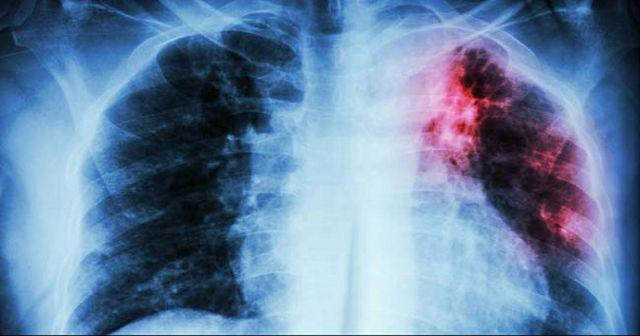

Sau khi kiểm tra, bác sĩ phát hiện Tiểu Lâm bị bệnh lao phổi, phần phổi đã bị vi khuẩn lao ăn mòn và xuất hiện nhiều lỗ thủng, nguyên nhân trực tiếp là do sức đề kháng thấp và lý do khiến hệ miễn dịch suy yếu chính là suy dinh dưỡng.

Phổi của Tiểu Lâm bị vi khuẩn lao ăn mòn, do cơ thể suy dinh dưỡng dẫn đến miễn dịch suy giảm và gây bệnh.